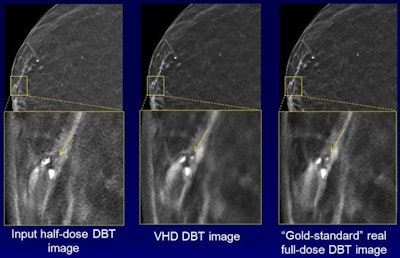

The images demonstrate how noise is reduced with the technique while the conspicuity of calcifications is maintained. Courtesy of Junchi Liu.Seven (70%) of 10 breast radiologists either preferred the virtual higher-dose DBT images over the real full-dose images or could not distinguish between the two, according to the group. The difference in image quality between the image types wasn't statistically significant (p = 0.59).

What's more, an observer study involving 10 breast radiologists and 10 clinical DBT cases found no statistically significant difference in quality between real full-dose images and the virtual high-dose images produced by the deep-learning algorithm from half-dose images.

"It reduced noise in half-dose images while preserving calcifications and breast tissue structures," Liu said.